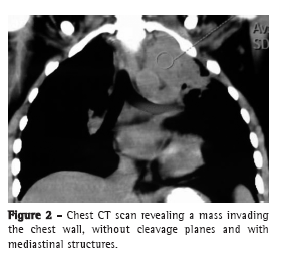

The patient was referred to the thoracic surgery department of our hospital for diagnostic investigation. Contrast-enhanced magnetic resonance imaging showed a mass with irregular borders, measuring 9.2 × 7.2 × 6.0 cm. The mass occupied the entire left upper lobe, invading the mediastinum and chest wall and involving the left common carotid artery, the left subclavian artery, and part of the aortic arch (Figure 1). A CT scan of the chest revealed invasion of the abovementioned structures and of the vertebral bodies, as well as the left supraclavicular fossa (Figures 2 and 3).

There are no radiological signs that are indicative of thoracic actinomycosis,(4) and chest X-ray findings can mimic a wide variety of diseases, including pulmonary infiltrate (suggestive of mild pneumonia) and micronodular infiltrate accompanied by pulmonary cavitation or large masses (suggestive of neoplasia), pleural effusion being common.(1,2,4,8,9) In advanced cases, a CT scan of the chest can reveal involvement of the chest wall, mediastinal involvement, and pleural involvement.(1,4,9) An image of diffuse involvement that crosses anatomical boundaries is highly suggestive of pulmonary actinomycosis.(4)